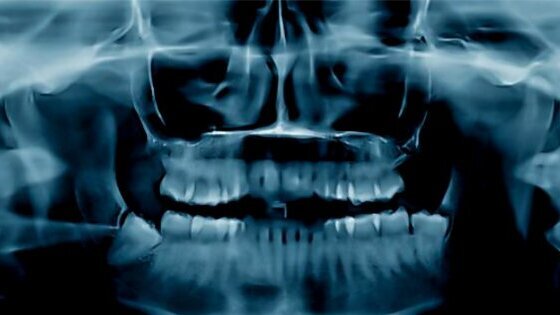

«L’osteonecrosi delle ossa mascellari ‒ spiega Fabio Vescini, Endocrinologia e Malattie del Metabolismo, Azienda Ospedaliero-Universitaria Santa Maria della Misericordia, Udine ‒ ha una patogenesi multifattoriale, all’interno della quale gioca un ruolo importante l’infezione dell’osso, caratterizzata da un’area esposta di tessuto osseo nel cavo orale che non guarisce entro 8 settimane dalla diagnosi. Negli ultimi 20 anni si è osservato che questo disturbo rappresenta una potenziale, rara, complicanza della terapia con bisfosfonati o con denosumab, utilizzati per il trattamento dell’osteoporosi, delle metastasi ossee e nella prevenzione della perdita di massa ossea in corso di blocco ormonale nei tumori della mammella e della prostata».

«Questo ha allarmato i pazienti che in alcuni casi mettono in discussione le cure con questi farmaci per timore della complicanza. Va subito detto che l’osteonecrosi, nei pazienti trattati per osteoporosi, è una malattia estremamente rara, si calcola infatti colpisca un paziente ogni 100.000 trattati per anno, ed è curabile con un trattamento odontoiatrico tempestivo, comprendente sempre la terapia antibiotica. Nella cura delle patologie scheletriche benigne, quali l’osteoporosi, i bisfosfonati vengono impiegati con dosaggi bassi, protratti nel tempo e sono assunti quasi sempre per via orale. Per quanto riguarda invece le patologie oncologiche (metastasi ossee), essendo necessarie dosi molto più elevate di farmaco, si ricorre a somministrazioni ravvicinate ad alti dosaggi: si calcola che un paziente trattato per un anno per metastasi ossee riceva una dose paragonabile a quella somministrata in circa 10 anni di trattamento per l’osteoporosi. In campo oncologico l’osteonecrosi delle ossa mascellari è più frequente e pertanto in questi pazienti è importante programmare periodici controlli dentali».